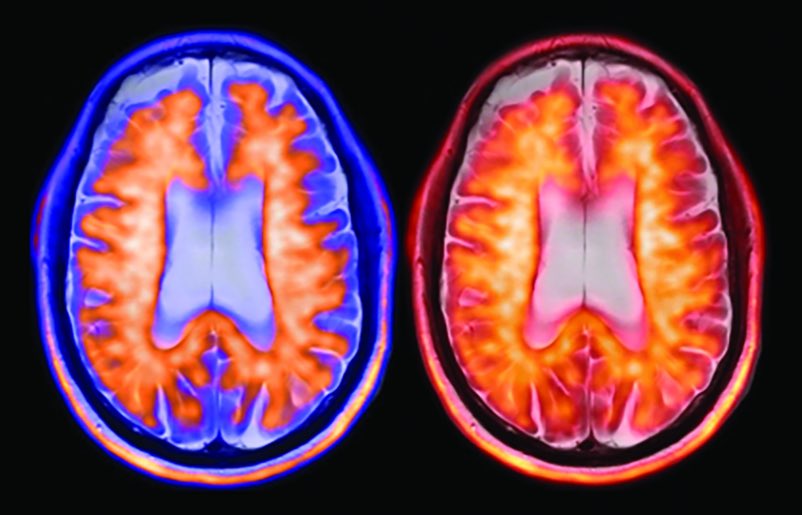

Another exciting milestone was reached this week in the #Alzheimer’s disease landscape! 👉𝗧𝗵𝗲 𝗯𝗶𝗴 𝗻𝗲𝘄𝘀: On Jan 26, 2025, Eisai US and Biogen announced FDA approval of IV maintenance dosing of once every 4 weeks for #lecanemab. For #AD maintenance therapy, once a

Another exciting milestone was reached this week in the #Alzheimer’s disease landscape!

👉𝗧𝗵𝗲 𝗯𝗶𝗴 𝗻𝗲𝘄𝘀:

On Jan 26, 2025, <a href="/EisaiUS/">Eisai US</a> and <a href="/biogen/">Biogen</a> announced <a href="/FDA/">FDA</a> approval of IV maintenance dosing of once every 4 weeks for #lecanemab. For #AD maintenance therapy, once a